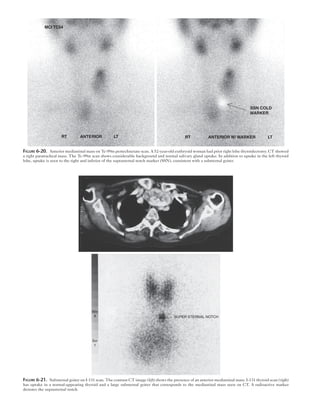

Uptake in substernal goiters is often lower than thyroid

bed activity. Tc-99m pertechnetate is not ideally suited for

this purpose because of its high mediastinal blood pool

activity, although the study can sometimes be diagnostic

(Fig. 6-20). I-131 has been used because it can be imaged at

24 to 48 hours and thus will have high target-to-background

ratio (Fig. 6-21). Currently, I-123 is usually the first radio-

pharmaceutical of choice with images obtained at 4 hours.

MCI TC04

RT ANTERIOR LT RT ANTERIOR W/ MARKER LT

SSN COLD

MARKER

Figure 6-20.  Anterior mediastinal mass on Tc-99m pertechnetate scan. A 52-year-old euthryoid woman had prior right lobe thyroidectomy. CT showed

a right paratracheal mass. The Tc-99m scan shows considerable background and normal salivary gland uptake. In addition to uptake in the left thyroid

lobe, uptake is seen to the right and inferior of the suprasternal notch marker (SSN), consistent with a substernal goiter.

SUPER STERNAL NOTCH

Figure 6-21.  Substernal goiter on I-131 scan. The contrast CT image (left) shows the presence of an anterior mediastinal mass. I-131 thyroid scan (right)

has uptake in a normal-appearing thyroid and a large substernal goiter that corresponds to the mediastinal mass seen on CT. A radioactive marker

denotes the suprasternal notch.